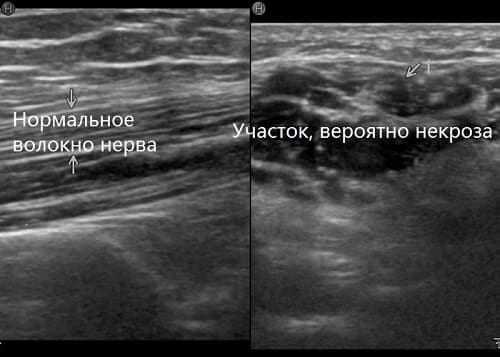

Патология требует тщательного исследования, установления причины и комплексного лечения. К сожалению, последствия нейропатии устранить сложно. В случае гибели участка нерва (некроза) или разрыва пучка – невозможно.

В случае травмы обязательно проводят УЗИ периферического нервного ствола. Дополнительно организовываются консультации с хирургами и травматологами. Могут потребоваться инструментальные обследования, чтобы увидеть состояние нервных тканей.